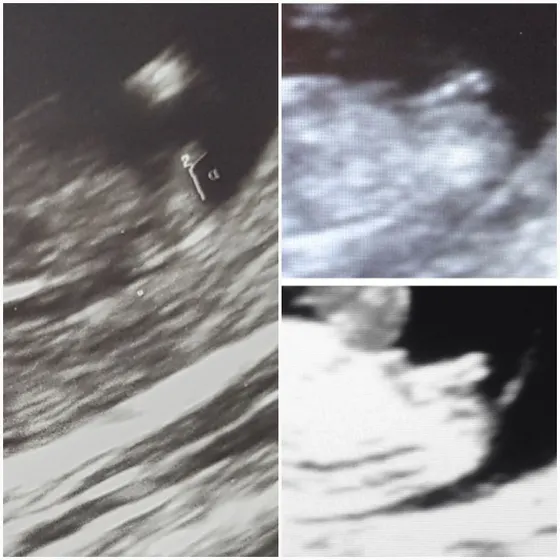

Привет мамули… слева половой бугорок моего пузожителя… справа те что 2 наверху и внизу одного и того же пузожителя я взяла из интернета… оба на 12 неделе… так вот девочки видите ли разницу… у кого подобные были и подтвердили пол тот что сказали на этой неделе..

А кого вам на узи предположили? Ну на втором и третьем фото точно мальчики)) а у Вас что-то мужского не видно, может подождать?

Те которые две там наоборот девочка. А вот мне 2 раза мальчика сказали один раз девочку..